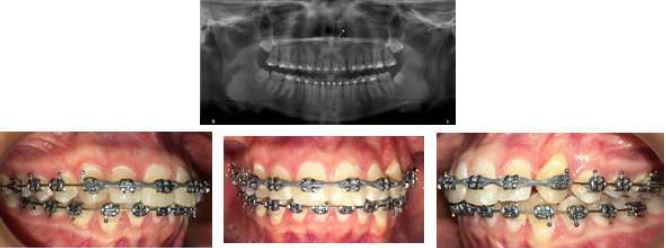

During the final recordings, tooth 23 had an adequate position and tooth 22 showed stable apical remodeling and a greater mesial root angulation (tip) when compared to previous radiographs (Figure 6).

Completion Records, Case 1

FIGURE 6

Source: the authors with permission from the patient.

Clinical and Radiographic Follow-up

An analysis of the control periapical radiographs showed a marked improvement in the path of eruption of both canines (Figure 10); therefore, teeth 53 and 63 were extracted and the patient was scheduled for surgery to change the traction vector of 23. Surgery was performed on the vestibular gingiva of 23, the button was relocated and a new chain was placed which was passed through the alveolus of 63. The flap was repositioned and sutured. A 0.017" x 0.025" TMA cantilever was installed on band auxiliary tube on 26. Both cantilevers were fitted with a distoclusal traction vector. In addition, open springs were placed between 14 and 12 and between 22 and 25 to expand the space and facilitate the accommodation of the canines (Figure 10).

Follow-Up Images, Caso 2

FIGURE 10

The radiographic image shows the new position of teeth 13 and 23. The repositioning of the direct cementation buttons and the new traction vector are also evident. Activation of the second-generation bilateral chains attached to the steel arm welded to the cemented bands on teeth 26 and 16 is also shown. Source: the authors with permission from the patient.

When reaching the most occlusal height, adhesion of 13 was performed and ligated at a distance with an elastic thread up to the arch. In 23, a palatal adhesion button was adhered and a chain installed to generate a coupler and derotate it (Figure 11). Once the rotation was resolved, a bracket was attached to 23 and continued to align until fully incorporated into the continuous arch. Likewise, the alignment of 13 and the lower teeth was completed (Figure 12).

Final Alignment Image of 13 and 23, Case 2

FIGURE 11

Final Records, Case 2

FIGURE 12